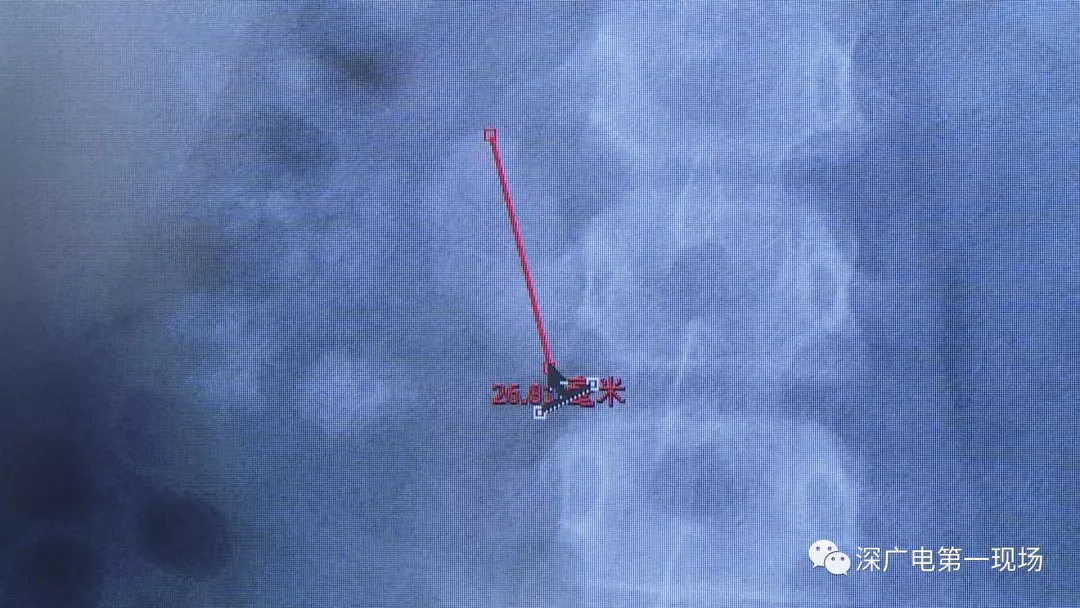

在X光圖像下,醫(yī)生發(fā)現(xiàn)小軒的雙側(cè)腎臟都內(nèi)藏乾坤,密密麻麻的分布著大小不等的結(jié)石。

醫(yī)生這么解釋:通常情況下,成人只要有0.5厘米大小的結(jié)石造成尿路梗阻,就需要及時治療。

小軒這種情況,其中,最大的結(jié)石長約2.7厘米,寬約1.7厘米,體積堪比鵪鶉蛋,不但造成了尿路堵塞,還導(dǎo)致了右腎中度積水。